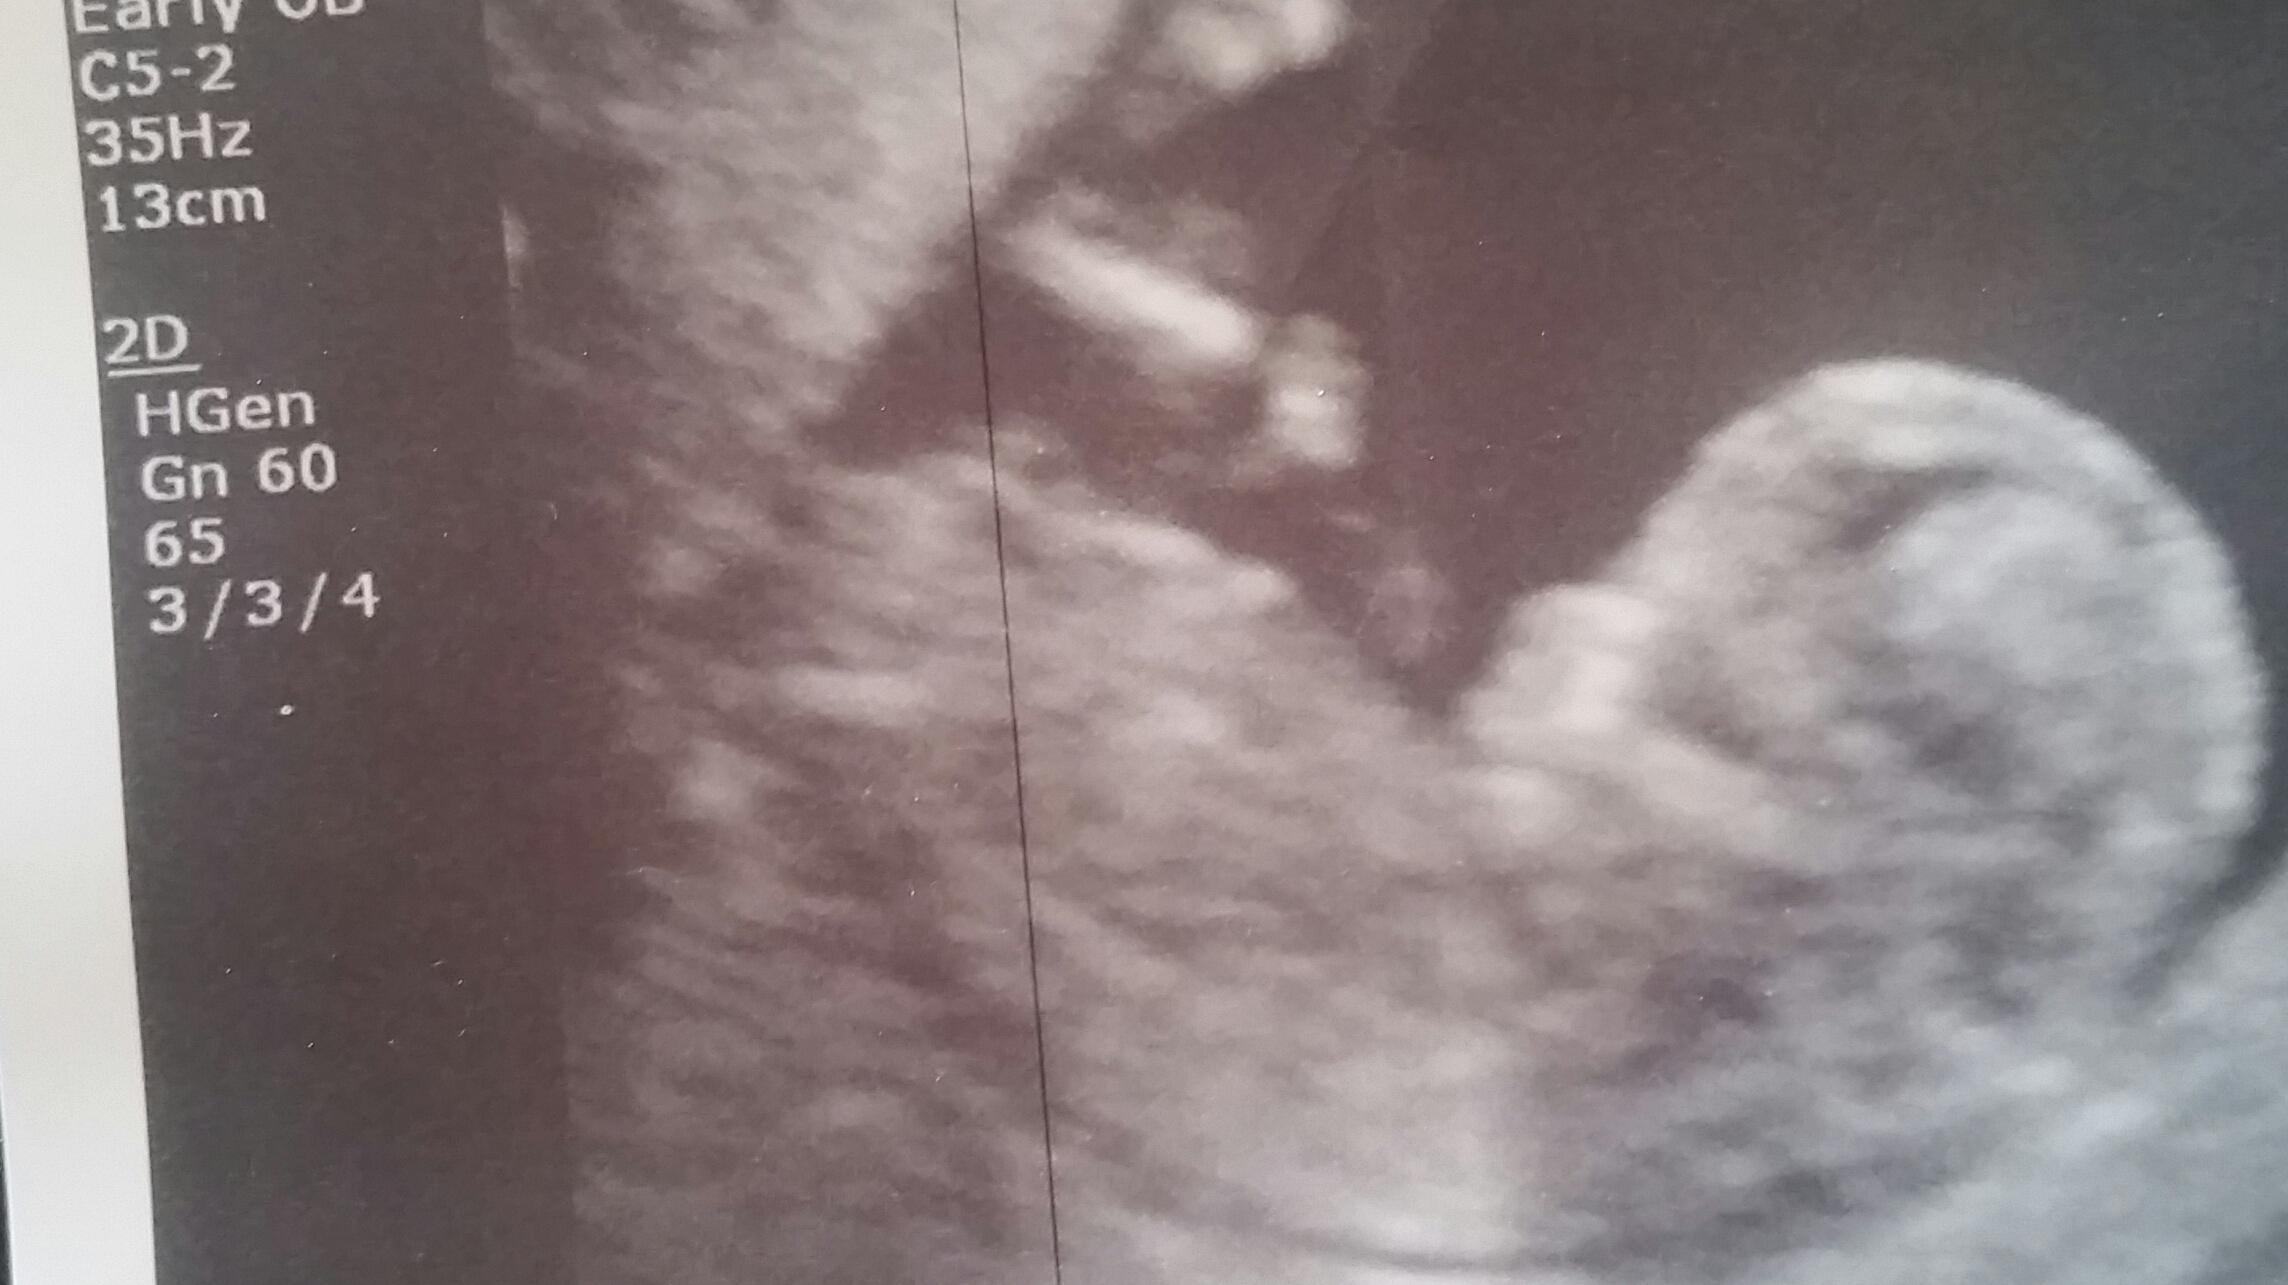

Any guesses?? :)

bump. Can someone show me where there is a nub in these pictures? Thanks!

how about this?

I am leaning girl..but just not sure with baby curled up.

Girl from the second pic you posted - the nub is the long white line below/following on from the abdomen x